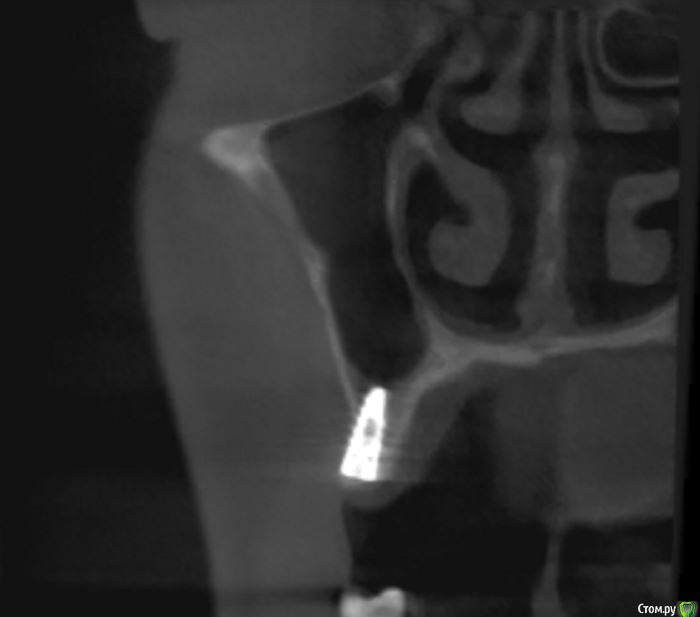

jm3300 Опубликовано 14 июля, 2016 Автор Поделиться Опубликовано 14 июля, 2016 выкладываю кт Ссылка на комментарий

умножающий печаль Опубликовано 14 июля, 2016 Поделиться Опубликовано 14 июля, 2016 Промыть пазуху через соустье, курсом. Я отправляю к ЛОРам. Антибиотикотерапия, гипосенсибилизация. Один из винтов вестибулярно без костной поддержки, на мой взгляд. 1 Ссылка на комментарий

red_butler Опубликовано 15 июля, 2016 Поделиться Опубликовано 15 июля, 2016 гайморит всё таки есть?Не увидел, один винт похоже на выход 1 Ссылка на комментарий

red_butler Опубликовано 15 июля, 2016 Поделиться Опубликовано 15 июля, 2016 Пазуха чистая, Антон, какой винт на выход не понял?Может у пац аллергия ?На последних срезах, вестибулярно на 2/3 кости нет.Какая уж аллергия, если боль и отек 1 Ссылка на комментарий

умножающий печаль Опубликовано 15 июля, 2016 Поделиться Опубликовано 15 июля, 2016 Тоже не понял, вроде все хорошо стоят. Главное слизистые то в покое.Это пока в покое. Винт не покрытый костью, долго под мягкими тканями оставаться не будет. Неизбежна рецессия со всеми вытекающими. 1 Ссылка на комментарий